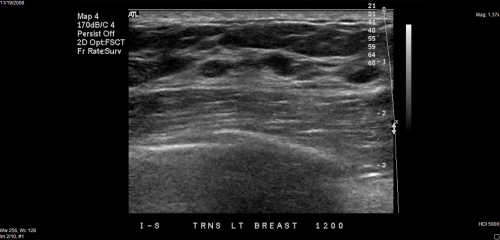

Axial (A) and coronal (B) ABUS images of the right breast show 4-mm irregular hypoechoic mass (arrows) at the 11-o’clock position. The background echotexture is heterogeneous. The mass was assessed as BI-RADS category 4. The patient underwent biopsy at a local hospital and subsequent surgical excision. Surgical histopathologic assessment revealed a 6-mm grade 2 invasive ductal carcinoma without axillary lymph node metastasis; the cancer was estrogen receptor positive, progesterone receptor positive, and HER2 negative. The case is consistent with cancer detected by ABUS screening.ARRS